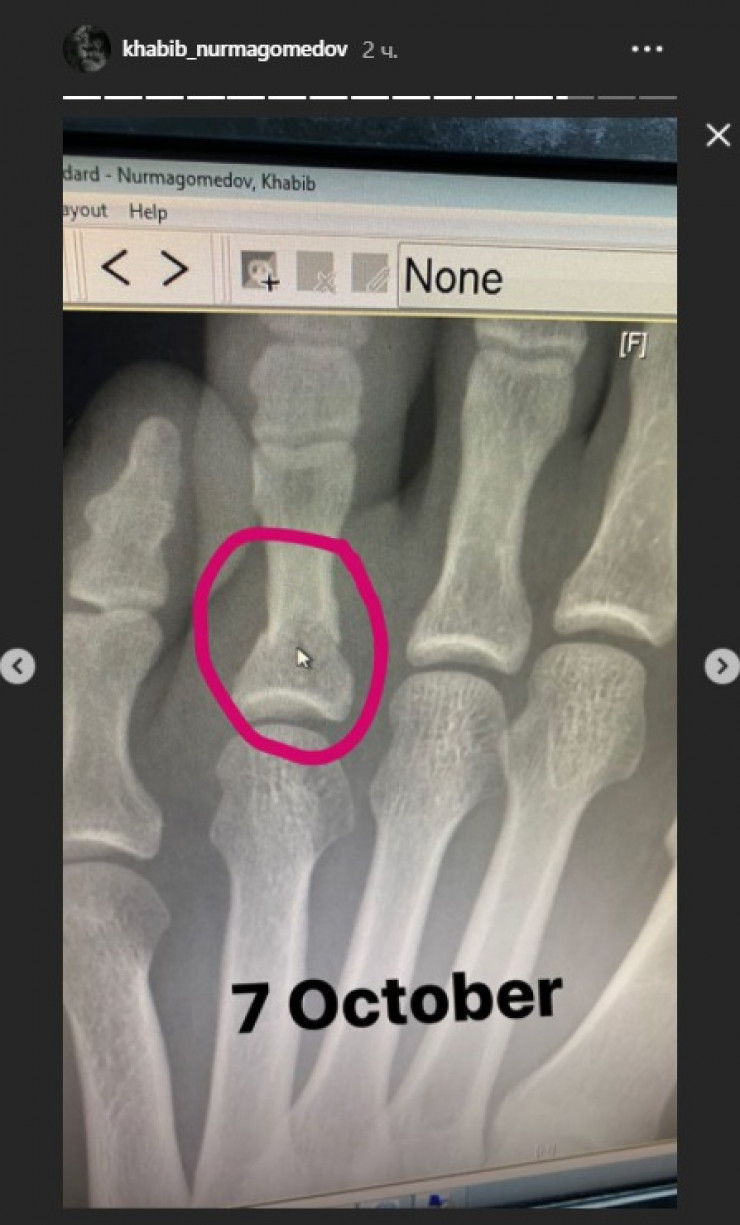

Российский чемпион UFC Хабиб Нурмагомедов опубликовал на своей странице в Instagram снимок перелома пальца ноги, который он получил перед боем с Гэтжи, передает Tengrinews.kz.

На фотографии, которую опубликовал Нургмагомедов, видны последствия травмы.

Россиянин также опубликовал рентгеновский снимок пальца ноги.

Ранее сообщалось, что за три недели до боя с американцем Джастином Гэтжи Хабиб Нурмагомедов обращался в больницу по поводу перелома.